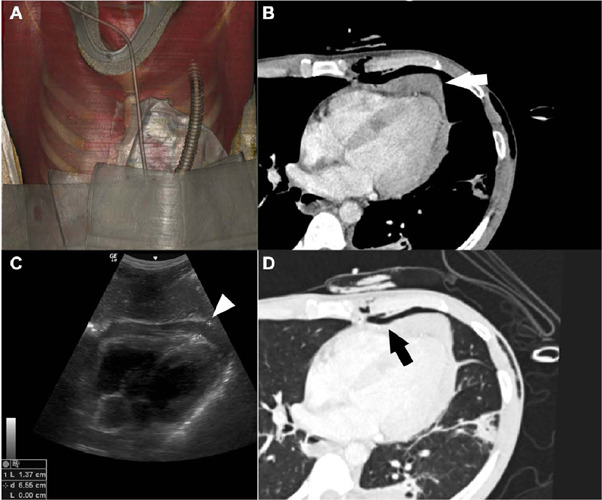

Abstract Image